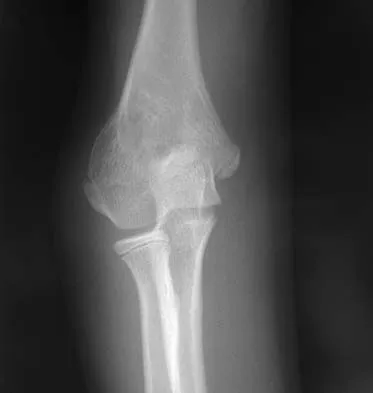

Figure 3 shows the radiographs of a 32-year-old man who fell 12 feet onto his outstretched arm and sustained a fracture-dislocation of the elbow. Initial management consisted of closed reduction of the dislocation. Surgical treatment should now include repair or reduction and fixation of the